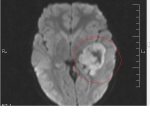

It was a busy day so we saw the physician’s assistant (PA) instead of Ian’s regular doctor. She was concerned that Ian might have bleeding in his brain from hitting his head. The PA ordered a CATscan to check for a concussion. Her final words haunt me still: “I don’t think it’s a tumor, but the scan should let us know what’s going on.”

Dr. Grabb seemed confident that it would be no big deal. “Brain tumors in children were a common occurrence; most of them were benign. The waiting is the hard part,” he said. “It seems to take forever for the results to come back from the lab.” He explained the small incision he would make above Ian’s left ear to remove the small egg-shaped tumor from Ian’s brain. The procedure would be two days later and would take about three hours. I hated the thought of Ian being operated on for so long.